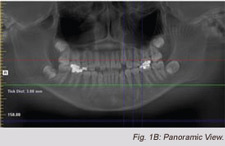

Records were taken, which included: traditional Facial and

Intraoral 2D photos, traditional study models and CBCT (i-CAT,

Imaging Sciences, Inter., Hatfield, Pennsylvania). A 2D lateral ceph

and 2D panoramic views were created from the 3D DICOM data

using i-CAT Vision software (Imaging Sciences).